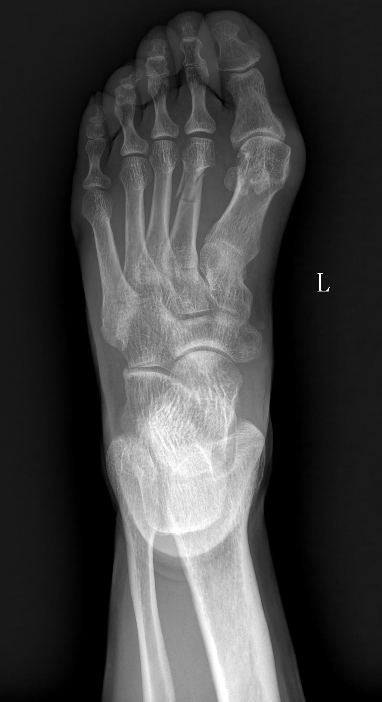

骨折后不到三个月,能否站上全马赛道?近日,马拉松业余跑者叶瑞用实际行动给出了答案。两个月前,她左侧第二趾骨骨折,右侧膝关节还伴有滑膜炎肿胀,在重庆医科大学附属康复医院的科学康复训练下,仅用不到三个月的时间,便顺利重返全马赛场,在湖北来凤马拉松中夺得女子组铜牌,凭借自身毅力与科学康复,实现了重返赛场的心愿。

作为一名马拉松业余跑者,叶瑞在日常训练过程中不慎左趾骨和右膝关节相继受伤。左侧第二趾骨骨折未愈,右侧膝关节又出现严重滑膜炎,肿胀与疼痛让她不得不暂时告别热爱的跑道。1月26日,叶瑞来到重庆医科大学附属康复医院综合康复科接受系统康复治疗及运动训练。针对复杂伤情,医院迅速组建由科室主任陈艳华博士领衔,主管医生欧阳俊琳、治疗师长王晶晶组成专项团队,量身定制分阶段、个体化、闭环式康复方案:康复初期,以消炎镇痛和物理因子治疗控制滑膜炎,缓解疼痛和肿胀;中期逐步引入下肢力量训练、平衡训练,打牢身体基础;后期结合步态分析,纠正跑步姿势,帮助叶瑞逐步恢复跑步能力,确保重返赛场的安全性。康复治疗师王晶晶全程负责具体治疗与训练指导,叶瑞也严格遵从康复计划,咬牙坚持、从不懈怠,全力配合每一项治疗与训练。

经过近三个月的系统科学康复,叶瑞的左侧趾骨骨折愈合良好,右侧膝关节滑膜炎症状缓解,关节功能恢复达到预期。得知叶瑞计划参加湖北来凤马拉松后,综合康复科团队特意为她提供了赛前指导,反复叮嘱她作为骨折康复后的首个全马赛事,务必量力而行,以完赛为首要目标,切勿急于求成、盲目激进,叶瑞将这份叮嘱牢记于心。